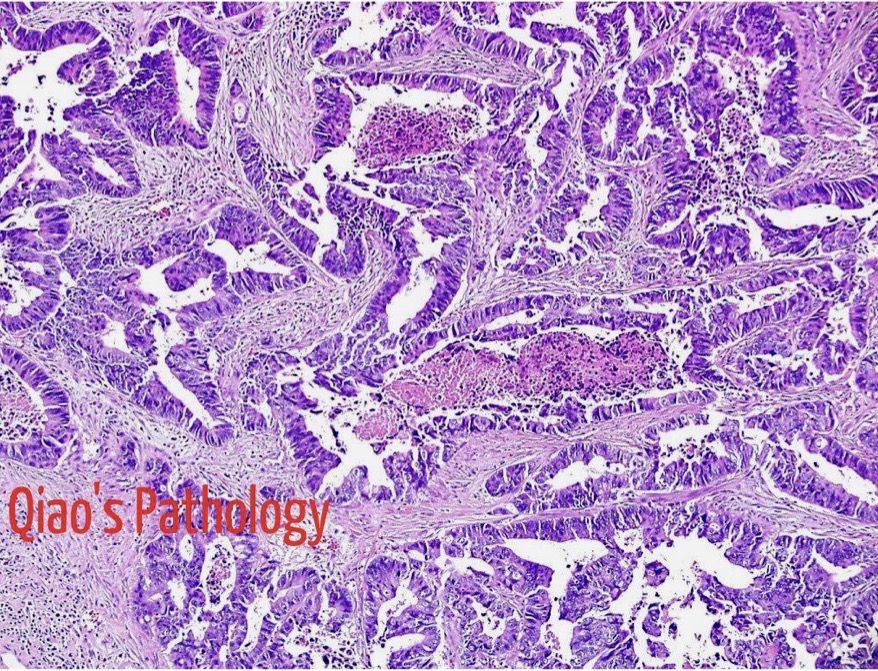

A- Colonic adenocarcinoma

B- The cancerous glands are irregular in shape and do not resemble the normal colonic glands. Their lining shows nuclear enlargement and hyperchromasia

C- from malignant epithelial tissue